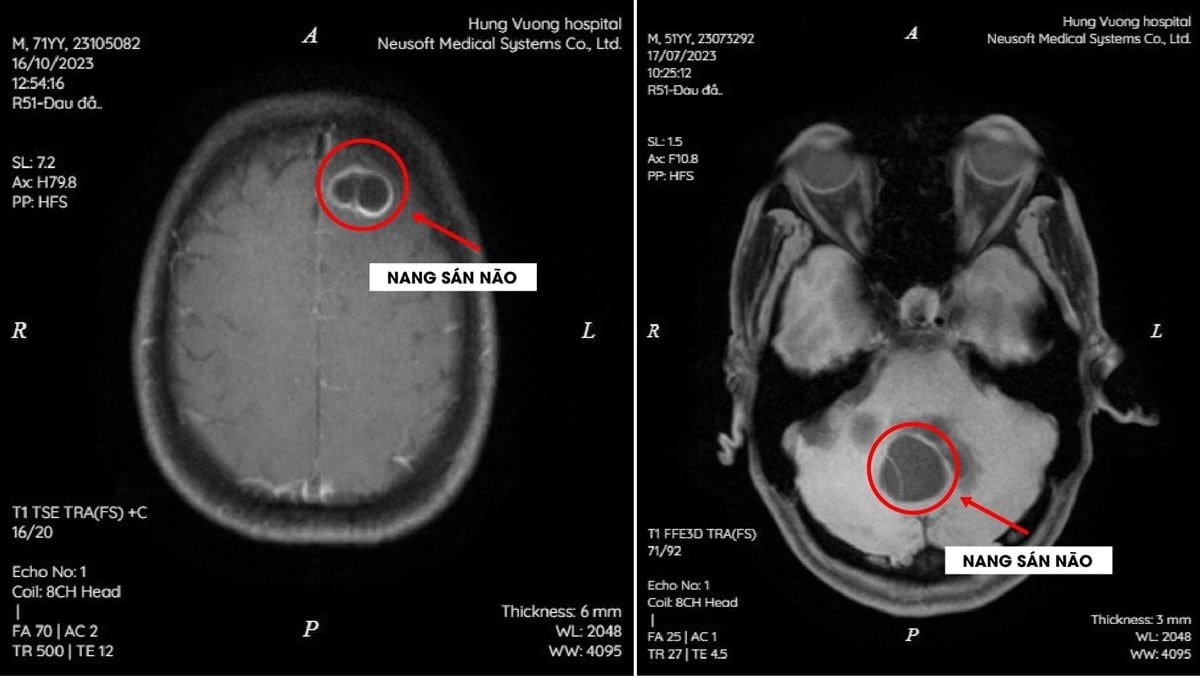

Không sốt, yếu liệt hay khó thở, song hình ảnh chụp CT cho thấy trong não bệnh nhân, sán dây chó đã kết thành nang lớn.

Kết quả chụp MRI sọ não của cả hai bệnh nhân cho thấy não tổn thương dạng nang trong nhu mô não theo dõi nang sán. Kết quả ELISA dương tính với sán dây chó (Echinococus).

Các bác sĩ chẩn đoán hai bệnh nhân trên bị Nang sán não (cerebral hydatid cysts) do sán dây chó (Echinococus). Nguyên nhân nhiễm sán do thường xuyên ăn tiết canh. Nếu không được phát hiện và điều trị kịp thời, bệnh nhân có thể bị liệt và các di chứng kèm theo.